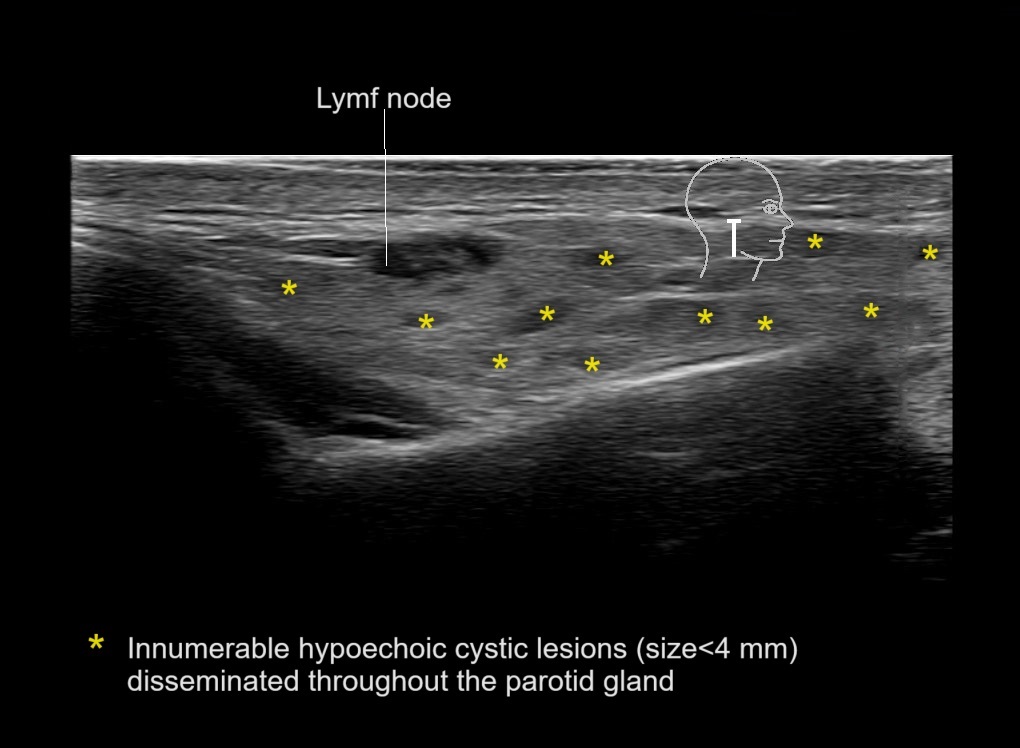

Study the first image to recognize the different layers. If you are sure about the layers, swipe to the second image to view the answer (if applicable).

Hover over an image to view the secondary image or click on the image title for more information.